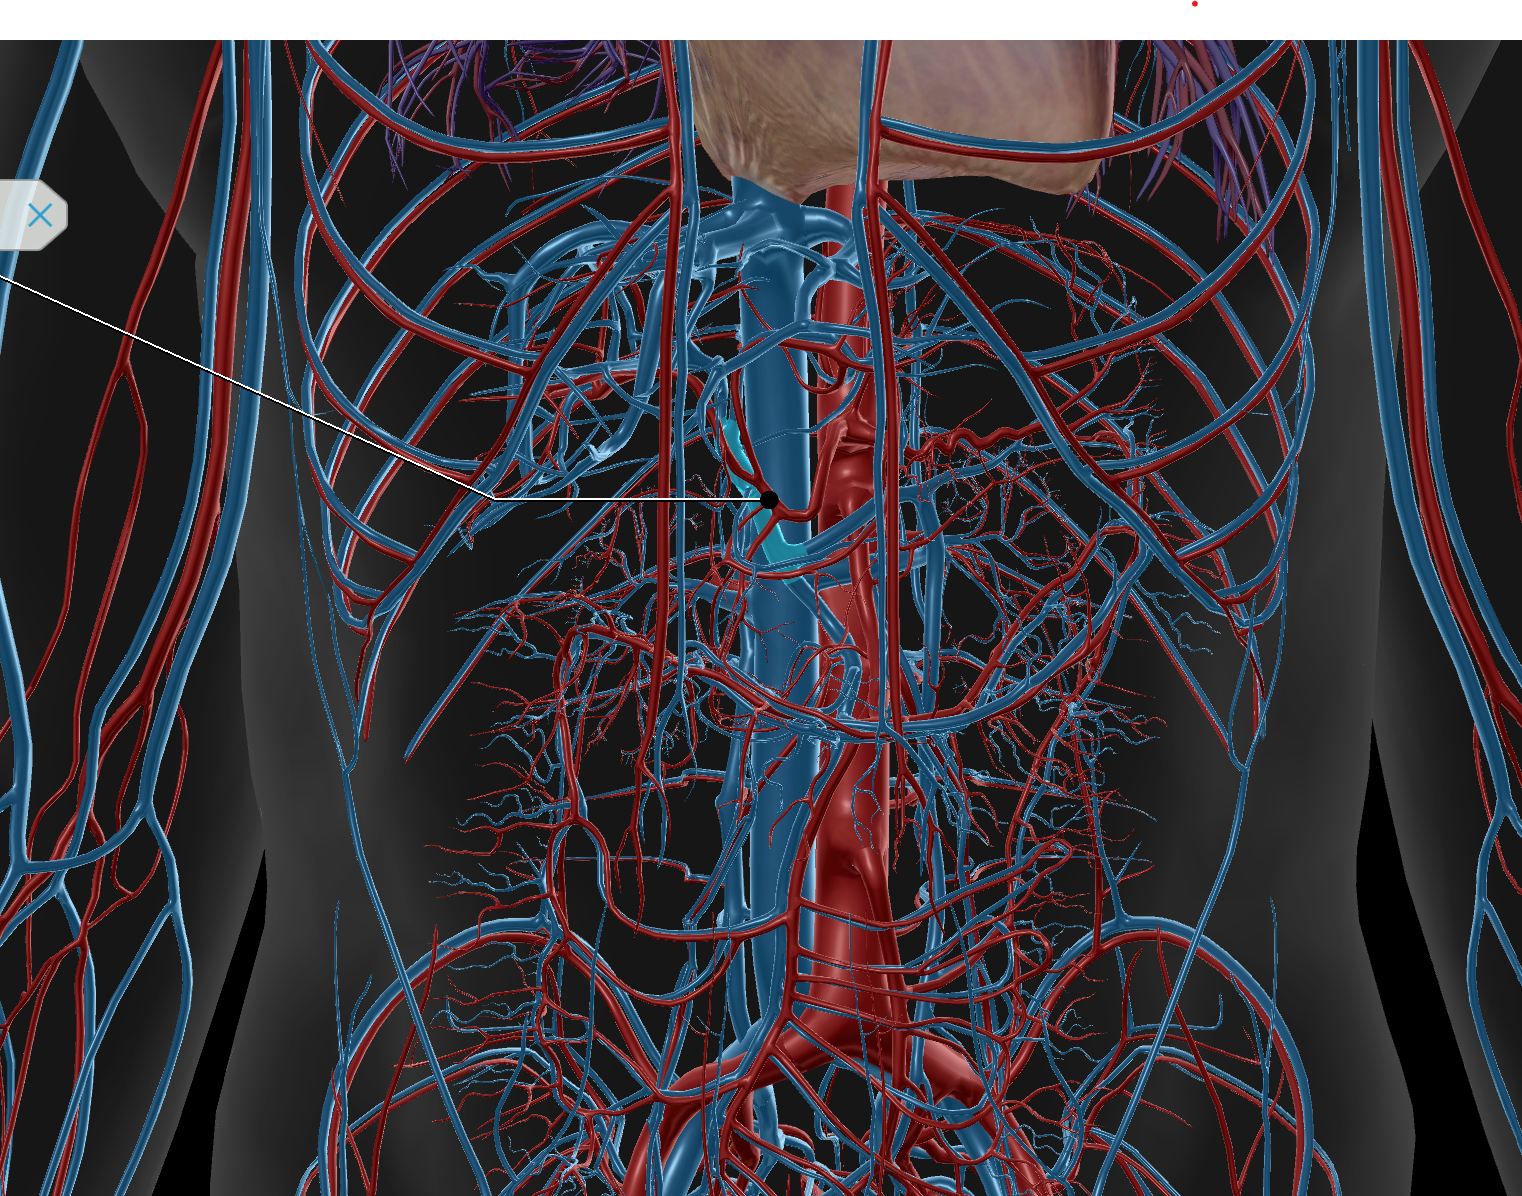

Inferior Vena Cava

Abdominal Aorta

Superior Mesenteric Artery

Renal Artery

Common Hepatic Artery

Celiac Trunk